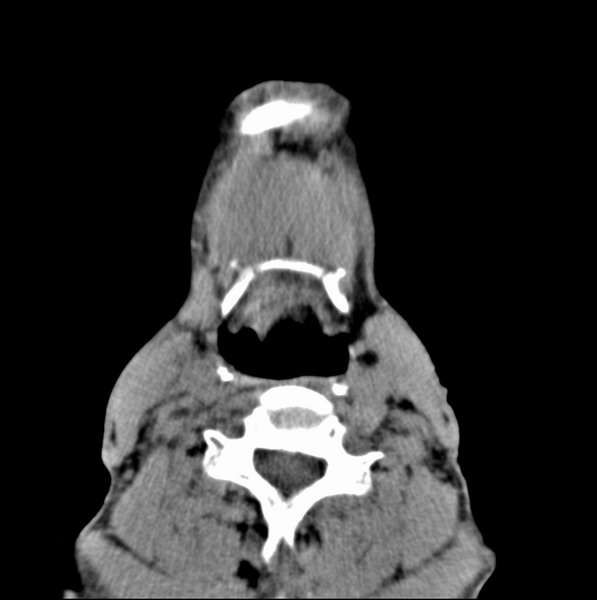

标题: CT19620:舌根肿物

男、60、舌根肿物。

舌垂直肌和横肌影处肿块影,边缘不规则,咽腭扁桃体及舌下间隙脂肪影消失,病变侵及口咽。

考虑-----舌根癌

舌跟软组织肿块,较大有坏死,钙化。结合年龄一般是恶性肿瘤。

舌根部较大软组织肿块,其内见坏死低密度区及钙化影;考虑舌根癌可能。